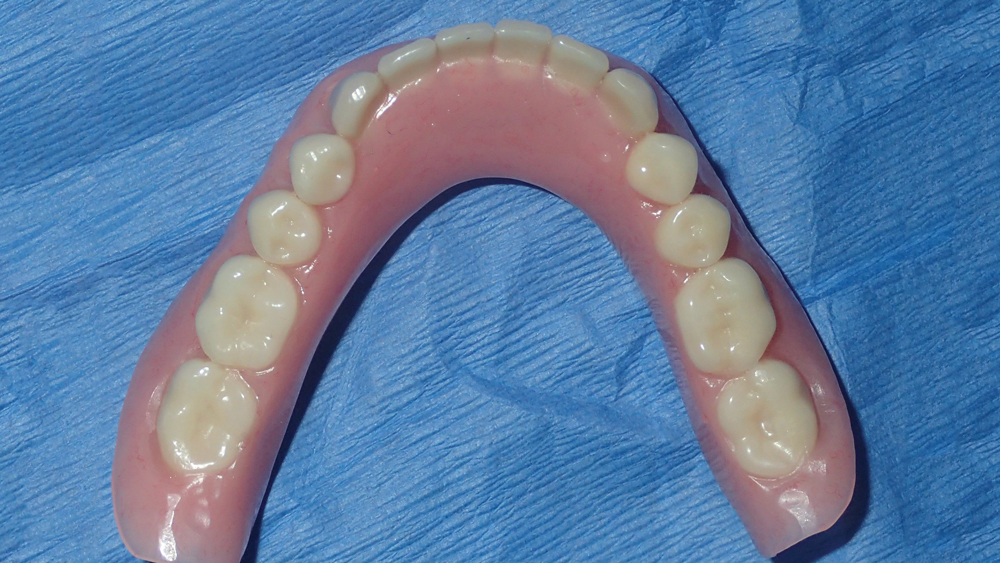

This patient was unhappy with the esthetics of her existing upper denture as well as the discomfort and instability caused by her loose-fitting mandibular partial denture. Although her concerns with the maxillary denture could be addressed with a new, more esthetic appliance, she preferred implant treatment for her mandible, where a fixed solution was needed to adequately restore function, stability and comfort.

The patient’s remaining mandibular teeth were extracted followed by immediate implant placement and delivery of a fixed provisional appliance. After integration of the implants, the prosthetic designs for the new upper denture and lower implant restoration were determined in tandem. Ultimately, the dual-arch restorations addressed the functional and esthetic challenges of the case while staying within the financial means of the patient, demonstrating the benefits of a flexible, multifaceted approach to restorative dentistry.